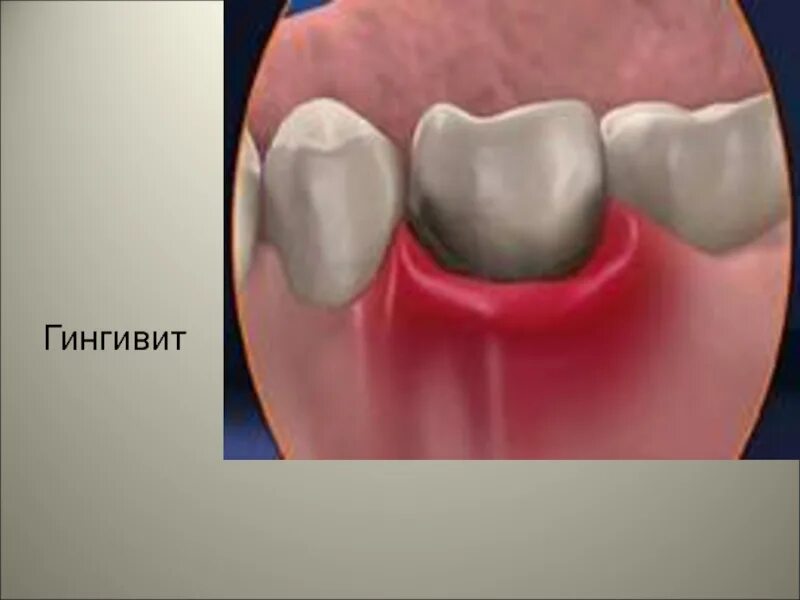

Зуб пульсирует и болит